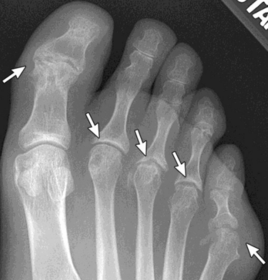

| What disease is this? | Rheumatoid arthritis |

| What disease is this? What do the arrows indicate? | Gout Arrows = 'punched out' erosions |